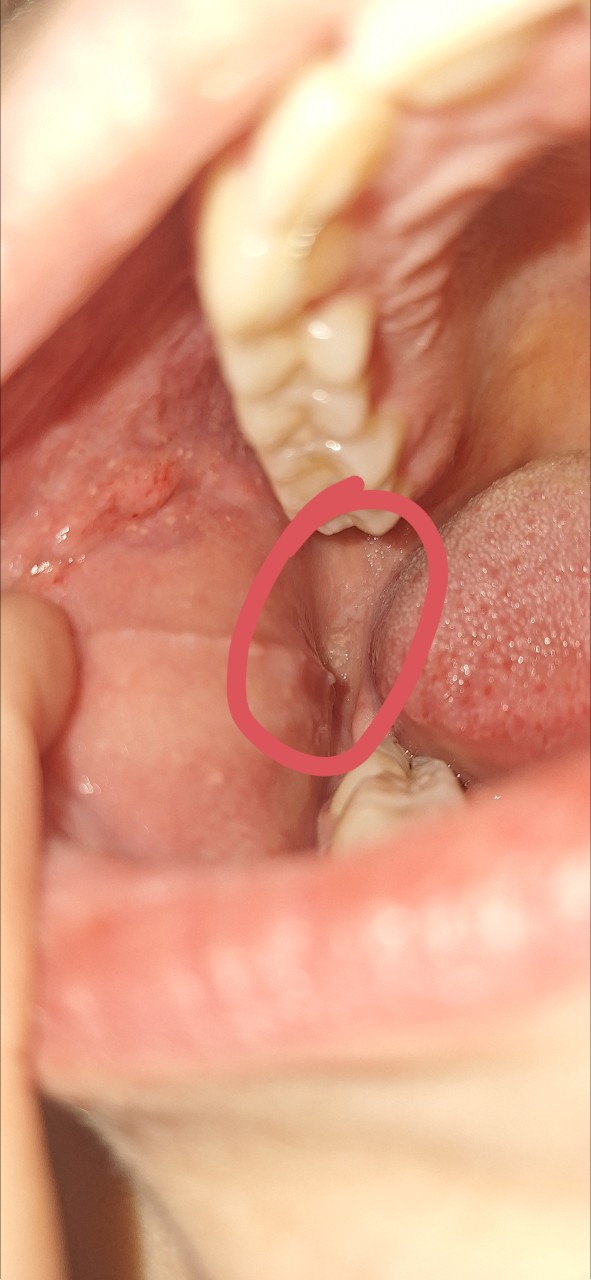

Немного болело горло, заглянула в рот, и справа увидела отекшее и красное на щеке, слева такого нет. Вот я и испугалась. Да, есть привычка, постоянно прикусываю, посасываю и лезу туда языком

На фото обвела, пугает вся эта зона, то что отличается от другой стороны, то что так весит, красная и отекшая.

Да, забыл добавить, там еще свисает, как сосочек — это место на слизистой щеки, где открывается устье выводного протока околоушной слюнной железы.

"Здравствуйте, подскажите пожалуйста, что это может быть на щеке? " - Там много чего есть. Желтые пятнышки — сальные железы, так называемые гранулы Фордайса. Есть красные точки — предположительно, из-за вредной привычки подсасывать щеку к зубам. По этой же причине можно увидеть так называемую "белую линию щеки".